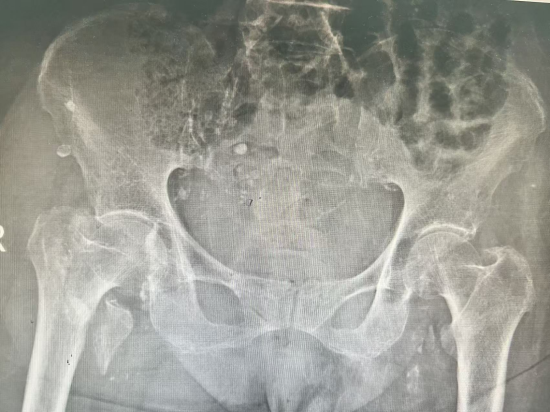

图1:入院时骨盆平片显示患者右侧股骨转子间骨折,骨质疏松

患者入院后,经检查确诊为右侧股骨转子间骨折。这一骨折被医学界称为“人生最后一次骨折”,因其多见于老年人,且卧床后易引发坠积性肺炎、静脉血栓、压疮等致命并发症,致残率、致死率极高,对百岁高龄的老人而言,更是一场生死考验。